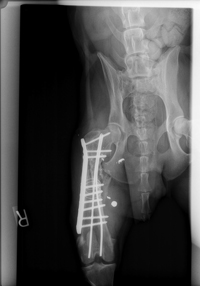

Femur

The carpenter wants to anatomically reconstruct the femur (gunshot wound in a 5-year-old German shepherd). Courtesy of Dr. Phil Zeltzman